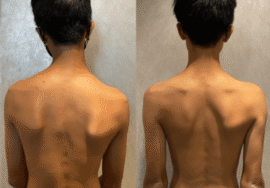

ما هو اعوجاج العمود الفقري؟ ولماذا يحدث؟

اعوجاج العمود الفقري هو انحناء جانبي غير طبيعي يظهر غالبًا في مرحلة الطفولة أو المراهقة، خاصة خلال فترات النمو السريع. في بعض الأحيان، لا يكون الانحناء ملحوظًا، لكن مع الوقت قد يؤدي إلى:

تغير في شكل الجسم.